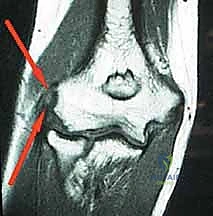

* الأشعة السينية (X-rays): لاستبعاد وجود التهاب مفاصل (خشونة) أو تكلسات عظمية.

* الرنين المغناطيسي (MRI): يُطلب في الحالات المزمنة التي لم تستجب للعلاج، لتحديد حجم التمزق في الوتر، واستبعاد مشاكل أخرى مثل انضغاط العصب الكعبري.

* إثبات وجود تمزق كبير في وتر (ECRB) عبر أشعة الرنين المغناطيسي.